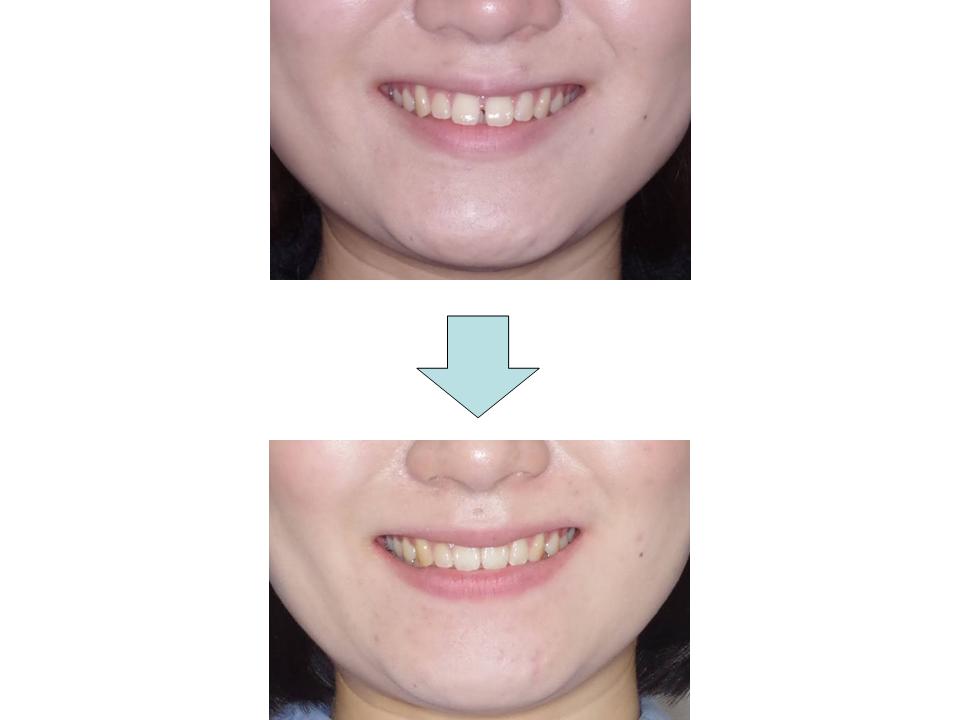

八重歯、上の前歯が出ている

上下前歯の凸凹が大きく、歯とあごの大きさのバランスの乱れを認めたため、上下の歯の抜歯を行って前歯の凸凹を改善しました。患者さんの装置装着状況も良好で上下の歯をきちんとかみ合わせることができました。

| 主訴 | 八重歯、上の前歯が出ている |

| 年齢・性別 | 30歳 / 女性 |

| 抜歯部位 | 上下顎両側第一小臼歯 |

| 装置 | マウスピース型矯正装置(インビザライン) |

| 期間 | 2年10か月 |

治療前

治療中

治療後

治療費840,000円

通院回数34回